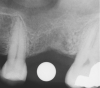

Once it is determined that the twist drill (2.1-mm diameter) is within 1 mm of the sinus floor, the second drill (2.8-mm diameter) and third drill (3.5-mm diameter), if desired, are used to penetrate to within 1 mm of the sinus floor (Figure 3). The amount of osteotomy widening is dependent upon tactilely perceived bone quality.

Figure 3  The osteotomy was completed with the 2.1-, 2.8-, and 3.5-mm twist drills without penetrating into the sinus.

Figure 3

Figure 4  After infracturing the subantral wall with a 3.5-mm osteotome, bone was added and the presence of a dome was confirmed with a radiograph.

Figure 4